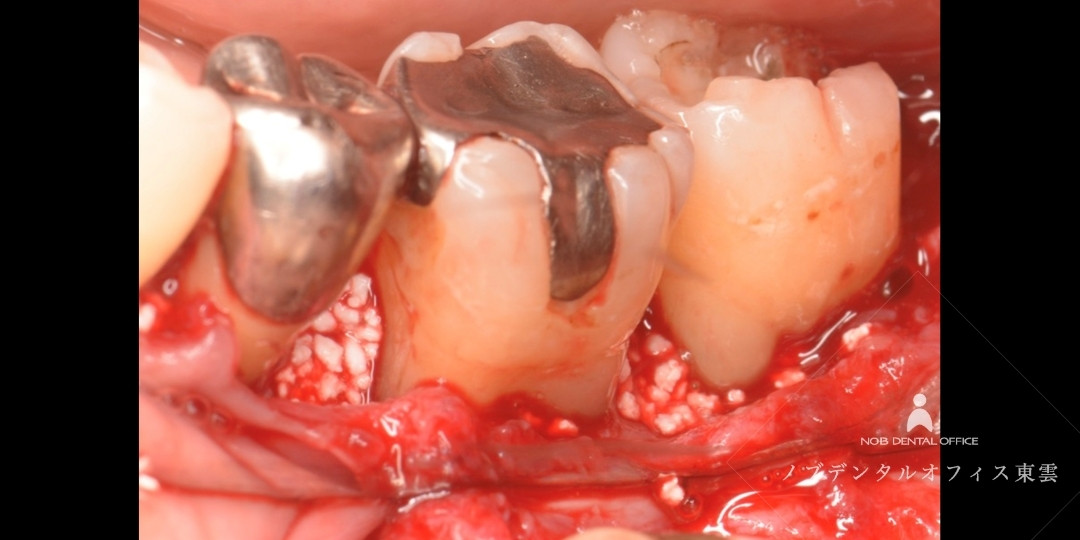

重度歯周病を自費診療で再生治療した症例(40代女性)

歯周病の治療をしたいと来院されました。

歯周基本治療を行いましたが、骨の吸収部分が大きかったため、自費診療にて歯周組織再生療法を行った結果、歯ぐきの状態が安定し、骨の回復傾向が確認されました。

レントゲンおよびCTにて、歯を支える骨の吸収が進行している部分が確認されました。

歯周基本治療後、骨吸収量が大きかったため、自費診療にて歯周組織再生療法(リグロス+骨補填材)を併用しました。

骨の吸収部分が大きかったため、CTにて3次元的に確認しました。

歯周組織再生療法では、汚れている部分を徹底的に除去し、リグロスと骨補填材を使用して、歯周再生療法を行いました。

汚れている部分を除去している様子

リグロスと骨補填材をセットした様子